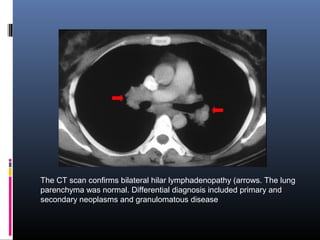

The CT scan confirms bilateral hilar lymphadenopathy (arrows. The lung

parenchyma was normal. Differential diagnosis included primary and

secondary neoplasms and granulomatous disease

The CT scanconfirms bilateral hilar lymphadenopathy (arrows. The lung parenchyma was normal. Differential diagnosis included primary and secondary neoplasms and granulomatous disease